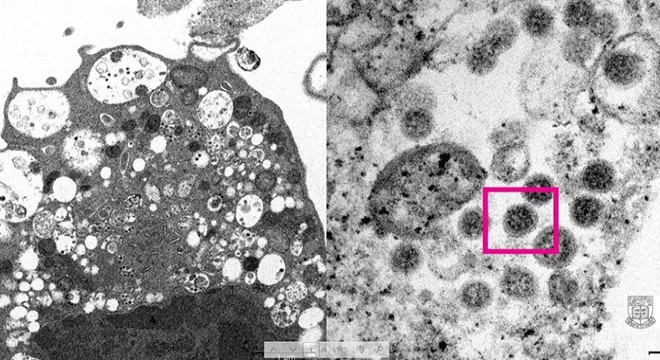

Omicron varyantının elektron mikroskobu görüntüsü yayınlandı

Hong Kong Üniversitesi Li Ka Shing Tıp Fakültesi (HKUMed) tarafından Omicron varyantının elektron mikroskobu görüntüsünün ortaya çıkarıldığı duyuruldu.

HKUMed’den yapılan açıklamada, araştırmacılar tarafından SARS-CoV-2 virüsünün Omicron varyantının elektron mikroskobu görüntüsünün ortaya çıkarıldığı belirtildi. Üniversite tarafından yayınlanan fotoğrafın solunda, küçük siyah viral partiküller içeren şişmiş veziküllerle hücre hasarını gösteren, SARS-CoV-2 Omicron varyantı ile enfeksiyondan sonra bir maymun böbrek hücresinin (Vero E6) düşük büyütmeli elektron mikrografının yer aldığı ifade edildi. Fotoğrafın sağında ise yüzeylerinde korona şekilli sivri uçlara sahip viral partikül kümelerini gösteren enfekte bir Vero E6 hücresinin yüksek büyütmeli elektron mikrografının yer aldığı belirtildi.